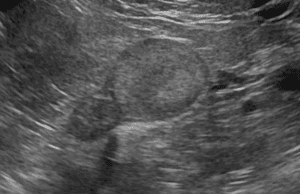

リンパ腫、乳腺腫瘍、肥満細胞腫などの腫瘍性疾患から、腎不全、尿路結石、膀胱炎、前立腺疾患などの腎泌尿器疾患まで、専門的な知見に基づいた診断と治療をご提供します。大切なご家族の病気に専門医が寄り添い、最適な治療をご提案できるよう努めてまいります。

腫瘍科外来

犬・猫のリンパ腫、乳腺腫瘍、肥満細胞腫などの腫瘍性疾患の診察と治療を行います。